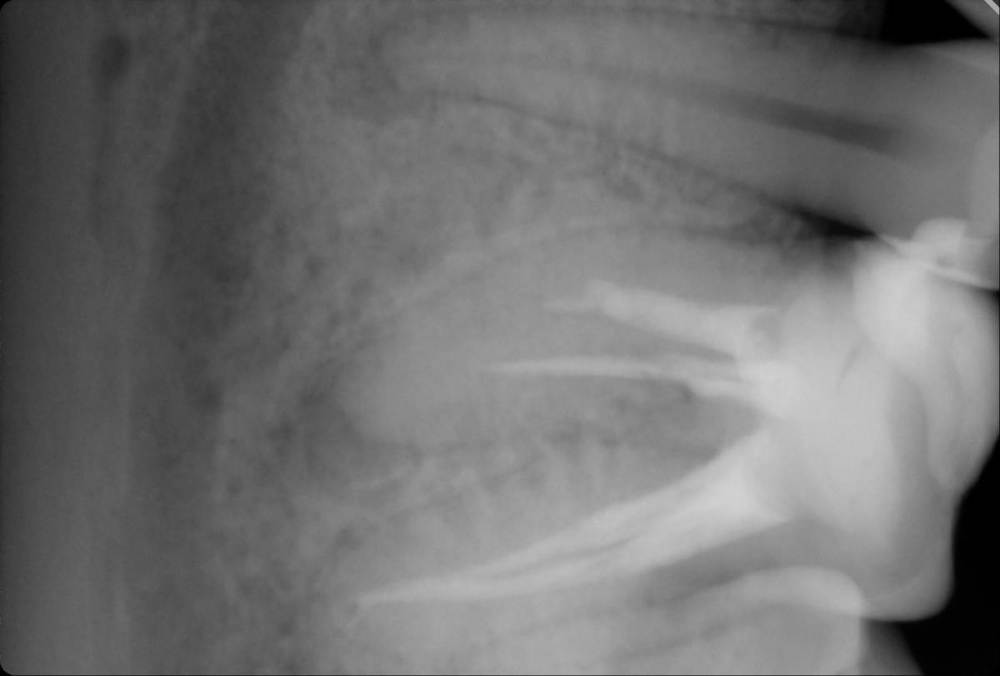

chacraborti Опубликовано 25 января, 2023 Поделиться Опубликовано 25 января, 2023 (изменено) Врач говорит что под пятеркой воспаление, квалифицирует зуб к лечению каналов. Прав ли врач? Можно ли вылечить воспаление иначе? Антибиотиками? Через кость? Через лунку при удалении рядом находящейся шестерки без нервов (она квалифицирована к удалению)? Субъективно время от времени в том районе чувствую слабую тупую боль которая может продолжаться несколько дней. потом исчезает, иногда стреляет(бывает раза 2 в день) время от времени, когда ем мороженное в том месте как будто щелкает Изменено 25 января, 2023 пользователем chacraborti Ссылка на комментарий

red_butler Опубликовано 26 января, 2023 Поделиться Опубликовано 26 января, 2023 5 часов назад, chacraborti сказал: Прав ли врач? если судить только по снимкам и Вашим жалобам то прав. Холодовую пробу проводили? 5 часов назад, chacraborti сказал: Через лунку при удалении рядом находящейся шестерки без нервов (она квалифицирована к удалению)? по снимкам вполне лечибельный зуб Ссылка на комментарий